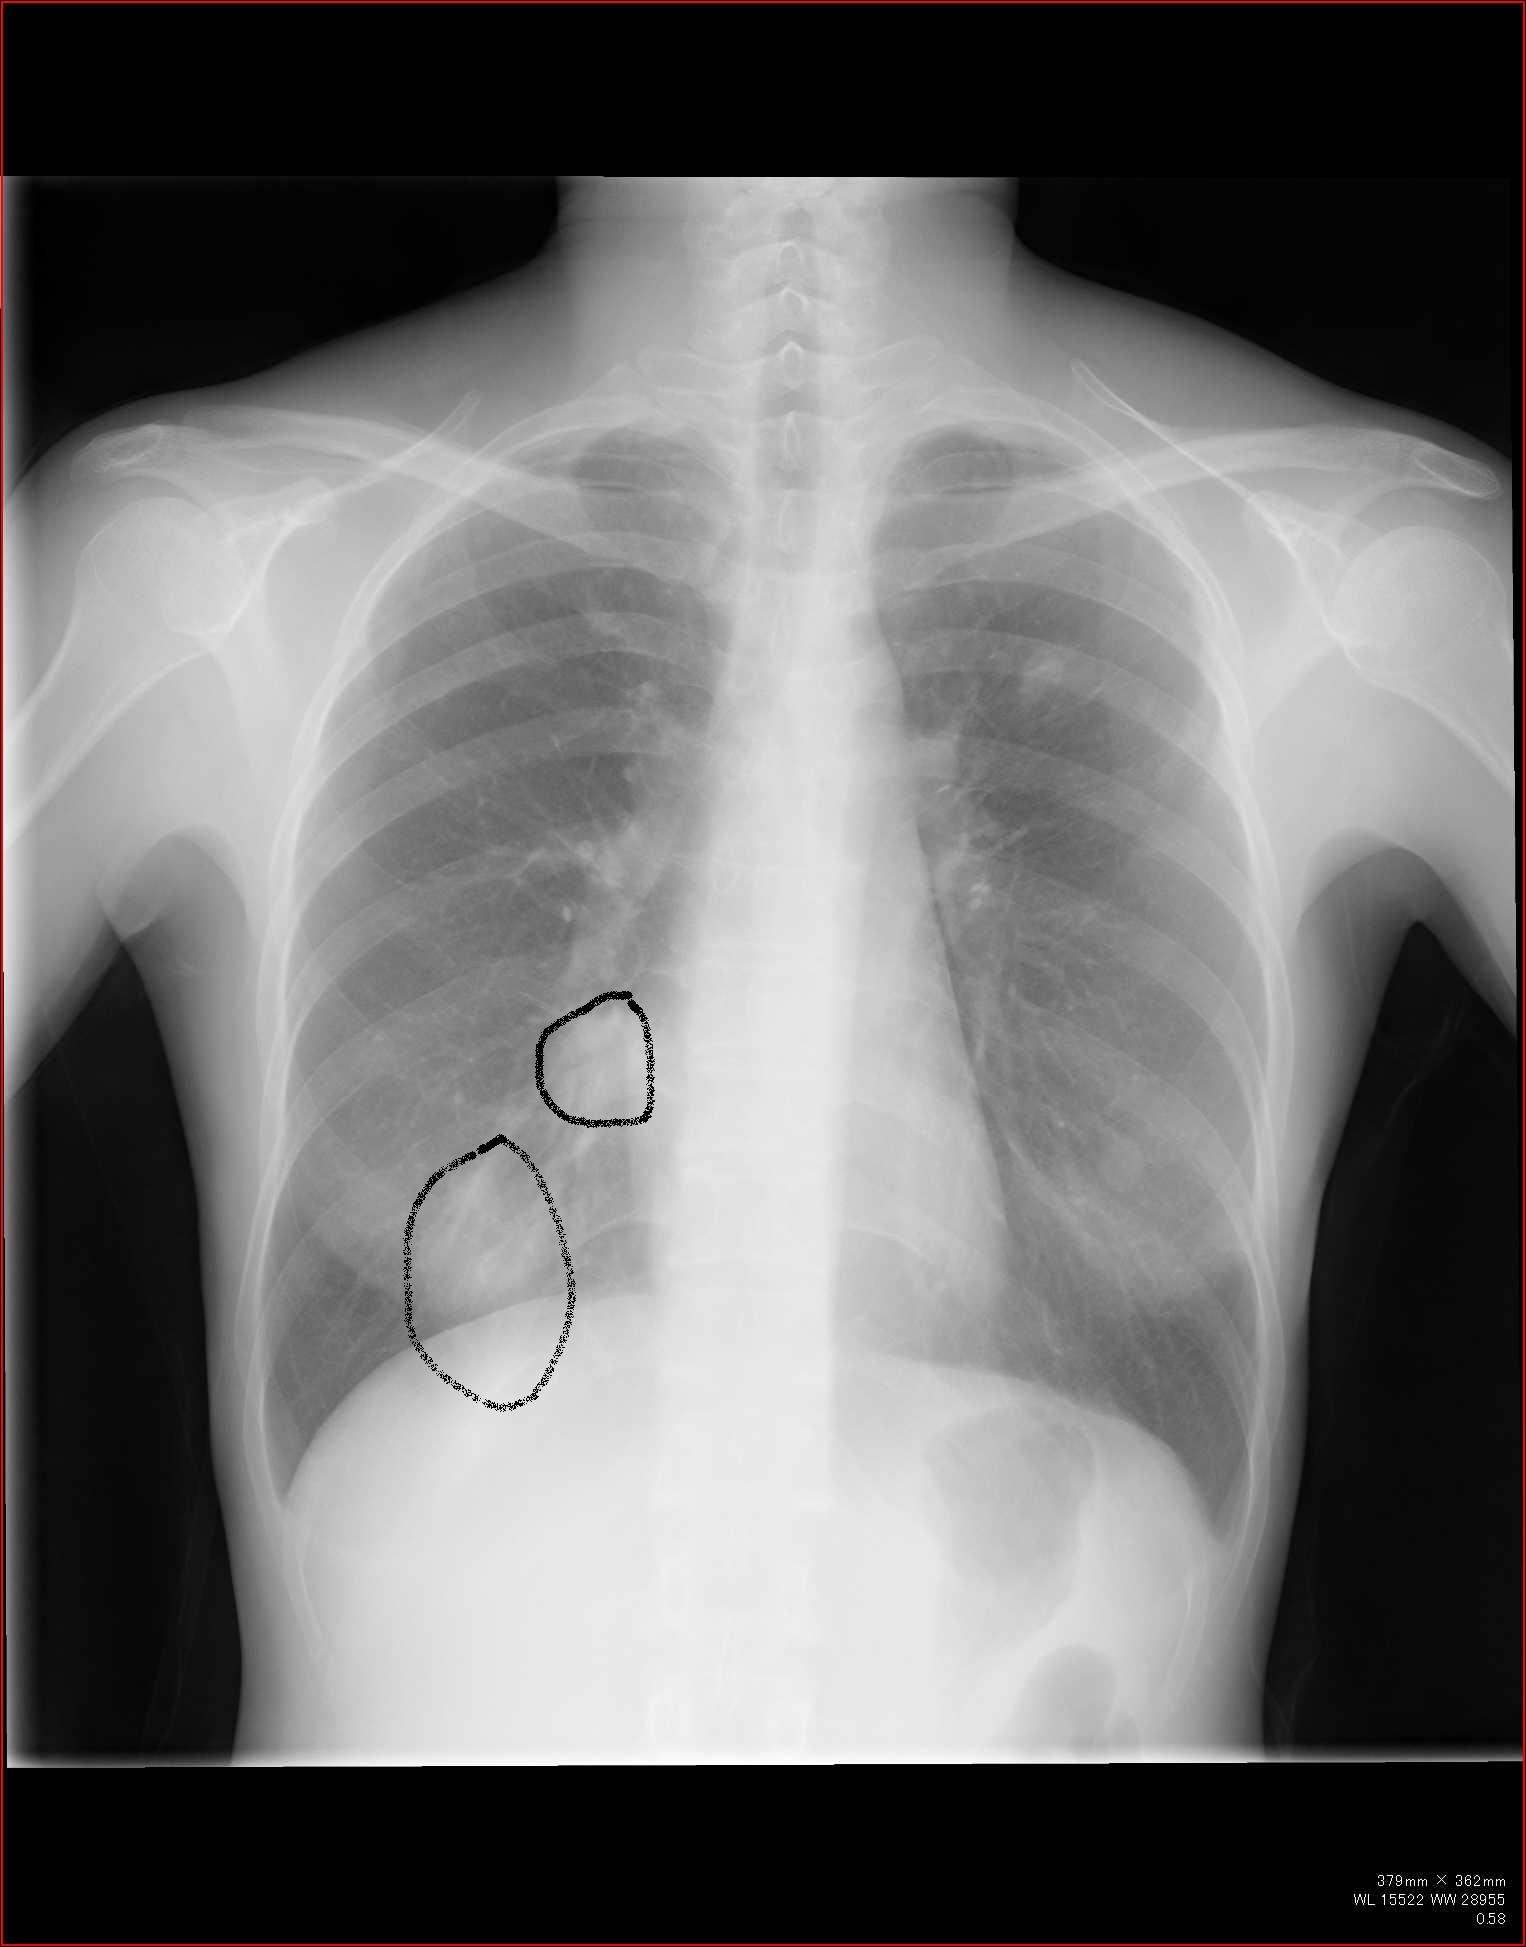

B正面像で見えるリンパ節

傍気管線、A-P window、気管分岐部は必ずチェックしましょう。